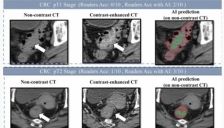

阿里巴巴达摩院联合医院发布肠癌筛查AI模型DAMO COCA,基于“平扫CT+AI”在2.7万份影像中实现86.6%敏感性、99.8%特异性,并识别出漏诊病例。该无创方案利用常规体检CT提升筛查接受度,助力早期发现肠癌、降低误诊漏诊风险。